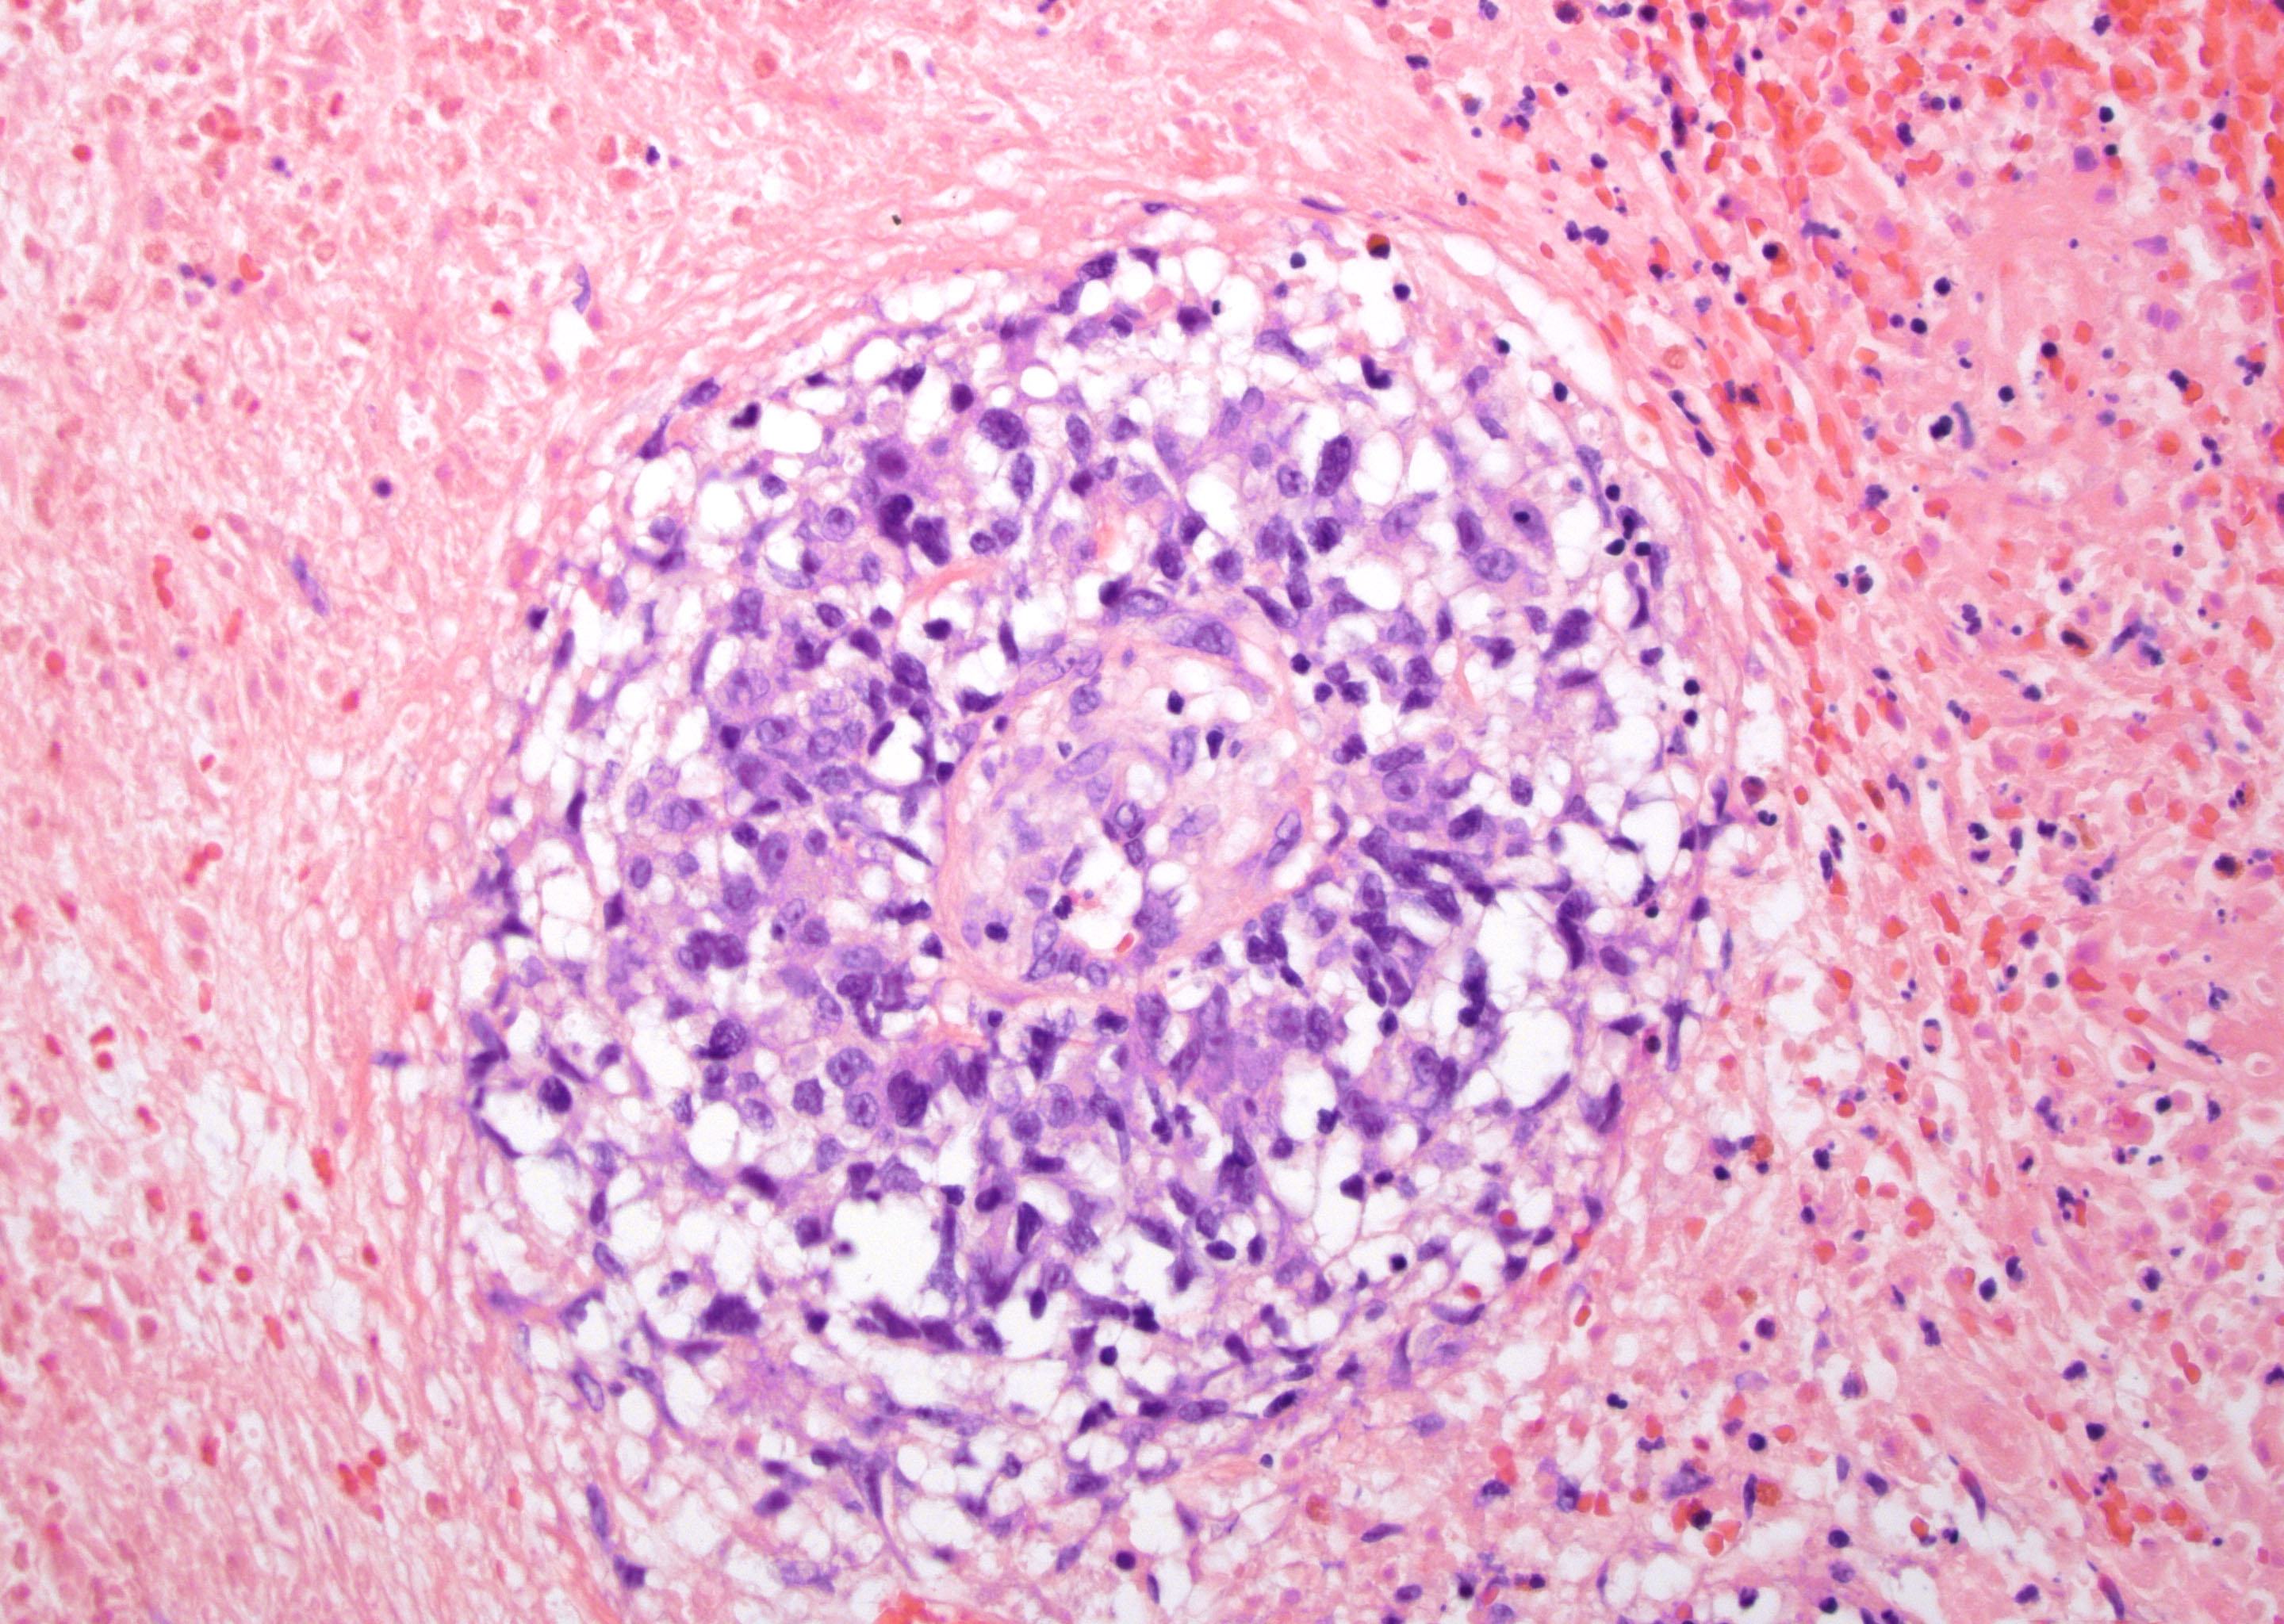

- Lymphomatoid papulosis is characterized by a wedge shaped pattern, with a wide superficial base and the tip at the bottom, usually deep dermis and less frequently into the subcutaneous tissue

- The most characteristic appearance is the presence of few to numerous large cells with a Hodgkin or Hodgkin-Reed Sternberg admixed with a reactive background of small lymphocytes and less frequently eosinophils, plasma cells and histiocytes

- Type A: wedge shaped and extensive lymphoid infiltrate with neutrophils, eosinophils and histiocytes; CD30+ cells are scattered and the overall histologic appearance mimics classic Hodgkin lymphoma

Microscopic (histologic) images

Contributed by Roberto N. Miranda, M.D.